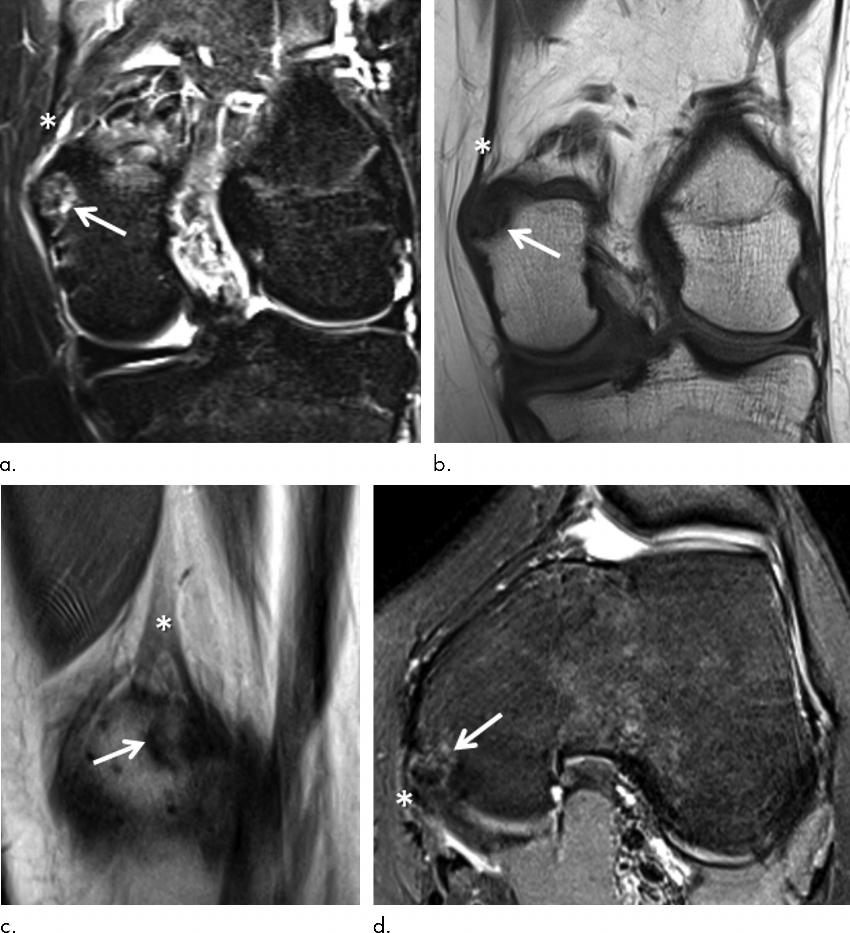

Figure 5. (a) Coronal short inversion time inversion-recovery, (b) coronal T1-weighted, (c) sagittal proton density– weighted, and (d) axial fat-suppressed proton density–weighted MRI scans in a 15-year-old female control participant show a distal femoral cortical irregularity (DFCI) (arrow) at the attachment of the adductor magnus tendon (*) at the adductor tubercle. The DFCI is 9 mm in diameter and shows a slightly expansive character.